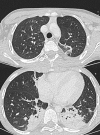

Results: We analyzed the data of 27 children. Comorbidities (n=19, 70%) were mainly neurological (n=7), respiratory, (n=4), or sickle cell disease (n=4). SARS-CoV-2 PCR results were positive in 24 children (nasopharyngeal swabs). The three remaining children had a chest CT scan consistent with COVID-19. Respiratory involvement was observed in 24 patients (89%). Supportive treatments were invasive mechanical ventilation (n=9), catecholamine (n=4), erythropheresis (n=4), renal replacement therapy (n=1), and extracorporeal membrane oxygenation (n=1). Five children died, of whom three were without past medical history.